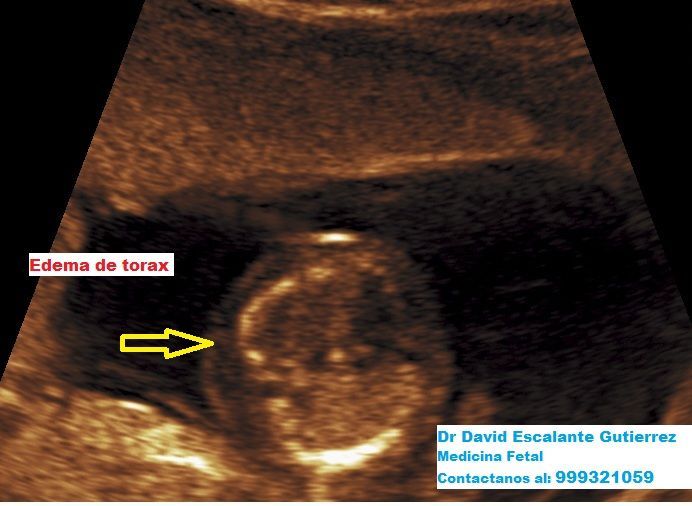

Realizamos las ecografías de viabilidad del embarazo, genética, morfológica, de bienestar fetal, ecocardiografías fetales, así como procedimientos invasivos como biopsia de vellosidades coriales y amniocentesis.